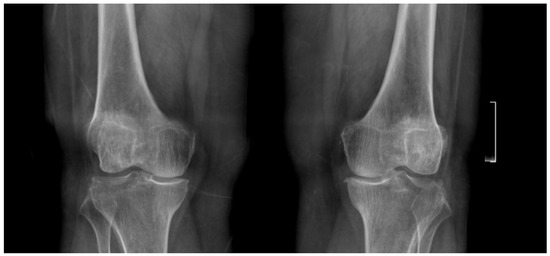

Her knee pain had persisted for several years and was unresponsive to conservative treatments, including physiotherapy and pharmacological pain management. She reported that the pain was continuous, affecting both day and nighttime, and was exacerbated by walking long distances and climbing stairs. Physical examination revealed a left knee varus deformity with a 5° fixed flexion contracture and a maximum flexion of 100°. Plain radiographs demonstrated advanced-stage osteoarthritis (OA) of both knee joints with mostly medial compartment involvement (Figure 1). After exhausting all conservative treatments, the patient was counseled and consented to undergo staged bilateral primary, elective TKA.

Figure 1.

Preoperative standing anteroposterior and lateral X-rays of both knees showing bilateral joint space narrowing and advanced osteoarthritic changes, more prominent in the medial compartment.